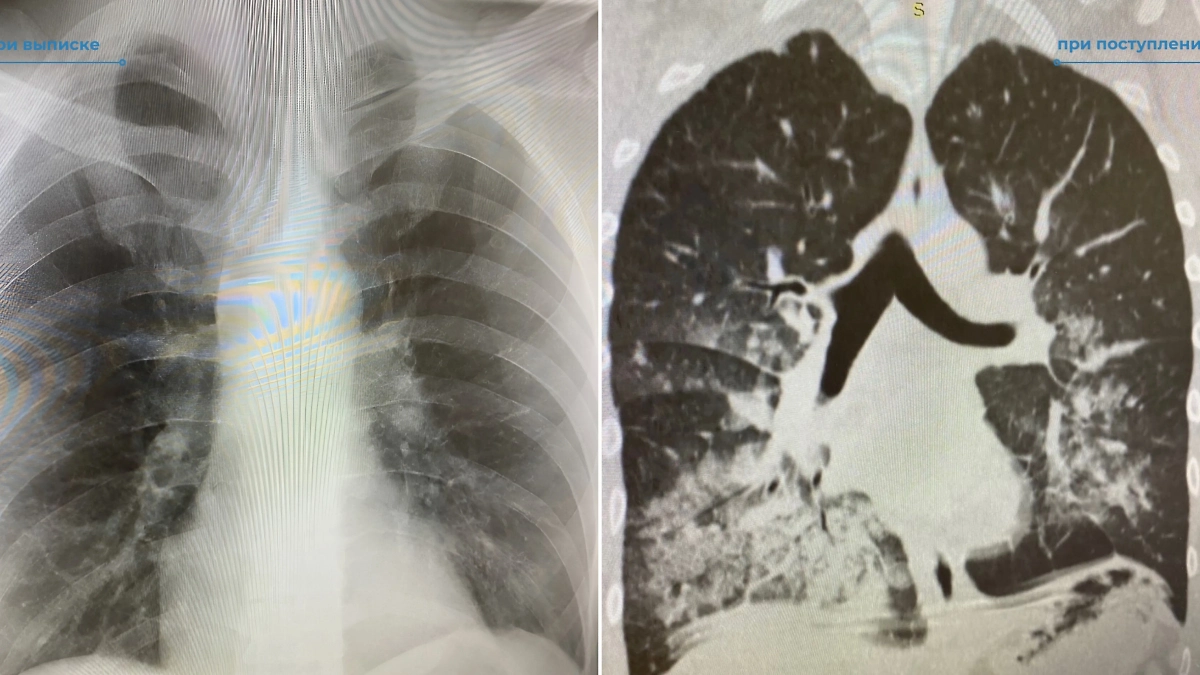

Лёгкие пациента после и до попадания в больницу. Фото © VK / Нижневартовская окружная клиническая больница

31-летнего местного жителя привезли в больницу в ужасающем состоянии, дышать ему удавалось с трудом. Стало известно, что это является следствием четырёхдневного распития алкоголя. Задыхающимся мужчину нашли его родственники, вызвавшие скорую помощь.

"У него всё сильнее нарастала дыхательная недостаточность, он стал кислородозависим и был переведён на ИВЛ", — сообщила заведующая отделением пульмонологии Ирина Семенюк.

Несколько суток вокруг него суетились врачи, что в итоге принесло свои плоды. Спустя время мужчина начал дышать самостоятельно. Сейчас его здоровью ничего не угрожает.